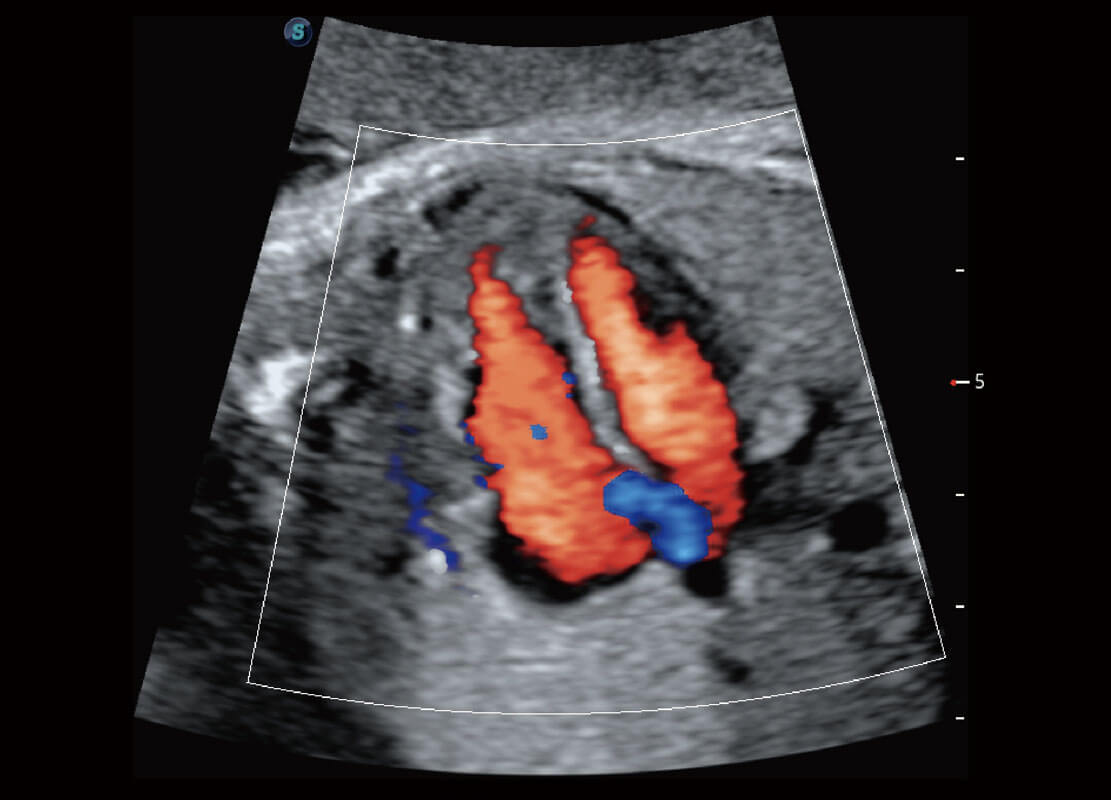

P60搭载一系列胎儿心脏成像技术,实现精细的胎儿心脏评估。

右室双出口

胎心容积成像